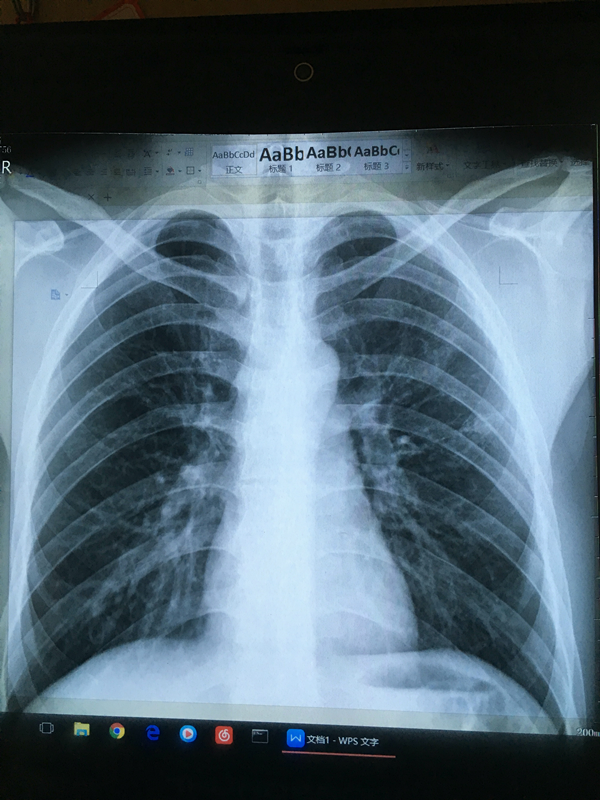

胸片

胸片

胸片

胸片

四年前得过肺结核后治愈要参加公务员体检了帮忙看下这张胸